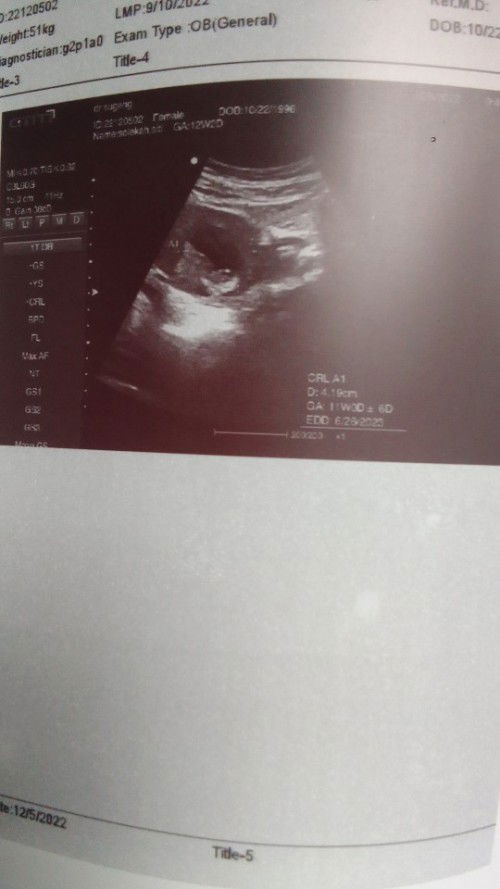

#seriusnanya Bun kalo di hitungan bidan bilang 12 week tapi di USG 11 itu gimana ya Bun trs itu hasilnya juga GK di jelasin baik cuma pas djj katanya bagus gitu doang kyk buru" bgt meriksanya soalnya hari ini Senin bnyk bgt pasienya